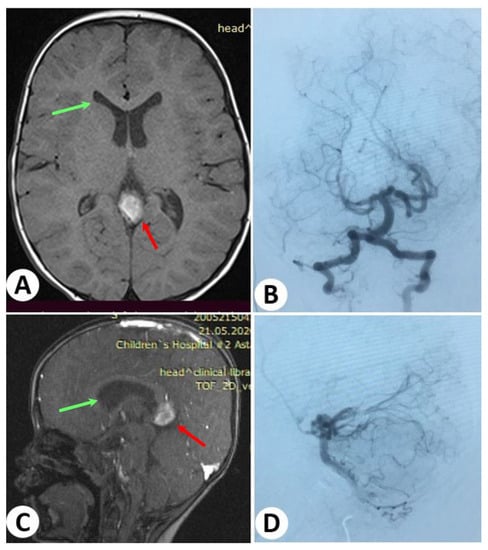

3.1. Illustrative Cases: Case 1

3.2. Illustrative Cases: Case 2